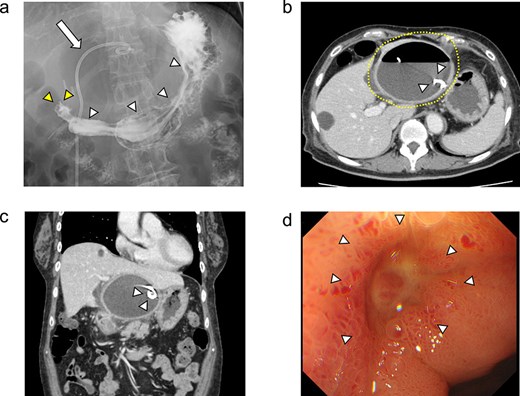

On day 13 of admission, an upper gastrointestinal contrast examination showed no obvious communication between the hepatic cyst and the duodenum (Fig. 2a). On day 20, CT showed that the hepatic cyst had tended to shrink but had not disappeared; in addition, the cyst wall had thickened (Fig. 2b). The CT also identified a low-density area between the hepatic cyst and the duodenum, which we suspected was a fistulous tract between them (Fig. 2c). On day 21, an upper gastrointestinal endoscopy revealed an ulcer scar at the anterior aspect of the duodenum bulb (Fig. 2d). A biopsy of the ulcer scar tissue revealed no malignancy.

The upper gastrointestinal contrast examination findings on day 13 of the patient’s hospital admission. (a) There was no obvious fistulous tract between the hepatic cyst and the duodenum. arrowheads: The stomach, arrowheads: The duodenum. arrow: The 7Fr pig-tail catheter. (b, c) Enhanced CT images findings on 20 day of admission. (b) Axial section. A shrunken hepatic cyst with a thickened cyst wall was observed. Dotted line: The large hepatic cyst. Arrowheads: The 7Fr pig-tail catheter. (c) Coronal section. A a low-density area was observed between the hepatic cyst and the duodenum, suspected of being a fistulous tract. Arrows: The low-density area between the hepatic cyst and the duodenum. Arrowheads: The 7Fr pig-tail catheter. (d) An upper gastrointestinal endoscopy on admission day 21 showed an ulcer scar at the anterior aspect of the duodenum bulb without obvious fistulous orifice. Arrowheads: The ulcer scar at the anterior aspect of the duodenum bulb.